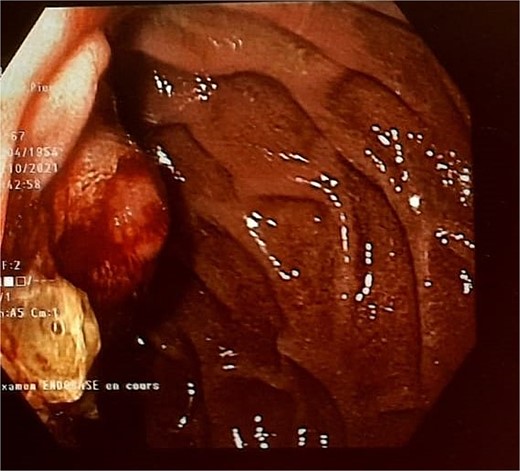

Endoscopic testing revealed a tissue lesion in the papilla (Fig. 1) and biopsies were positive for adenocarcinoma of the ampulla of Vater. An abdominal CT scan revealed dilatation of the Wirsung duct. The right gastroepiploic artery (RGEA), gastroduodenal artery (GDA), and right gastric artery (RGA) were not involved. The work-up for extension—including an MRI, 3-phase CT scan, and PET-CT scan—ruled out any distant lesions. Based on these results and after multidisciplinary discussion, it was decided to perform surgery since the clinical stage was cT2N0M0.